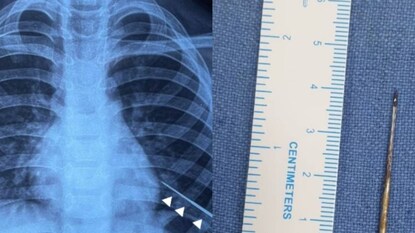

ഏഴ് വയസ്സുകാരന്റെ ശ്വാസകോശത്തിൽ നിന്ന് സൂചി പുറത്തെടുത്ത് ഡോക്ടർമാർ. ഡൽഹി ഐയിംസിലാണ് ശസ്ത്രക്രിയ നടന്നത്. കഴിഞ്ഞ ബുധനാഴ്ച്ചയാണ് കുട്ടിയെ ആശുപത്രിയിൽ പ്രവേശിപ്പിച്ചത്. കാന്തം ഉപയോഗിച്ചാണ് സൂചി പുറത്തെടുത്തത്. എങ്ങനെയാണ് സൂചി ശരീരത്തിനുള്ളിലേക്ക് കടന്നത് എന്നതിനെ കുറിച്ച് വീട്ടുകാർക്കോ കുട്ടിക്കോ അറിയില്ലെന്നാണ് സൂചന.

കടുത്ത പനിയും രക്തം ചുമച്ച് ഛർദ്ദിക്കുകയും ചെയ്തതിനെ തുടർന്ന് കുട്ടിയെ ആദ്യം സ്വകാര്യ ആശുപത്രിയിൽ പ്രവേശിപ്പിക്കുകയായിരുന്നു. ഇവിടെ നിന്നാണ് എയിംസിലേക്ക് മാറ്റുന്നത്. എക്സ് റേയിൽ ഇടത് ശ്വാസകോശത്തിൽ സൂചി കണ്ടെത്തി. ശ്വാസകോശത്തിൽ ആഴ്ന്നിറങ്ങിയ നിലയിലായിരുന്നു സൂചിയുണ്ടായിരുന്നത്. ശസ്ത്രക്രിയ ഉപകരണങ്ങൾ ഉപയോഗിച്ച് പുറത്തെടുക്കാൻ സാധിക്കാത്തതിനെ തുടർന്നാണ് കാന്തം ഉപയോഗിച്ചതെന്ന് ഡോക്ടർമാർ പറയുന്നു.

ഇടതു ശ്വാസകോശത്തിനുള്ളിൽ സൂചിയുടെ കൃത്യമായ സ്ഥാനം കണ്ടെത്താൻ എൻഡോസ്കോപി നടത്തി. സൂചിയുടെ അഗ്രഭാഗം മാത്രമേ ഇതുവഴി കാണാൻ സാധിക്കുകയുള്ളൂ. ഇതിനു ശേഷം കാന്തം ഘടിപ്പിച്ച ഉപകരം സൂക്ഷ്മതയോടെ സ്ഥാനത്തേക്ക് കയറ്റി. കാന്തത്തോട് സൂചി പെട്ടെന്ന് അടുക്കുകയും വളരെ വേഗത്തിൽ പുറത്തെടുക്കാൻ സാധിച്ചുവെന്നും ഡോക്ടർ പറഞ്ഞു.